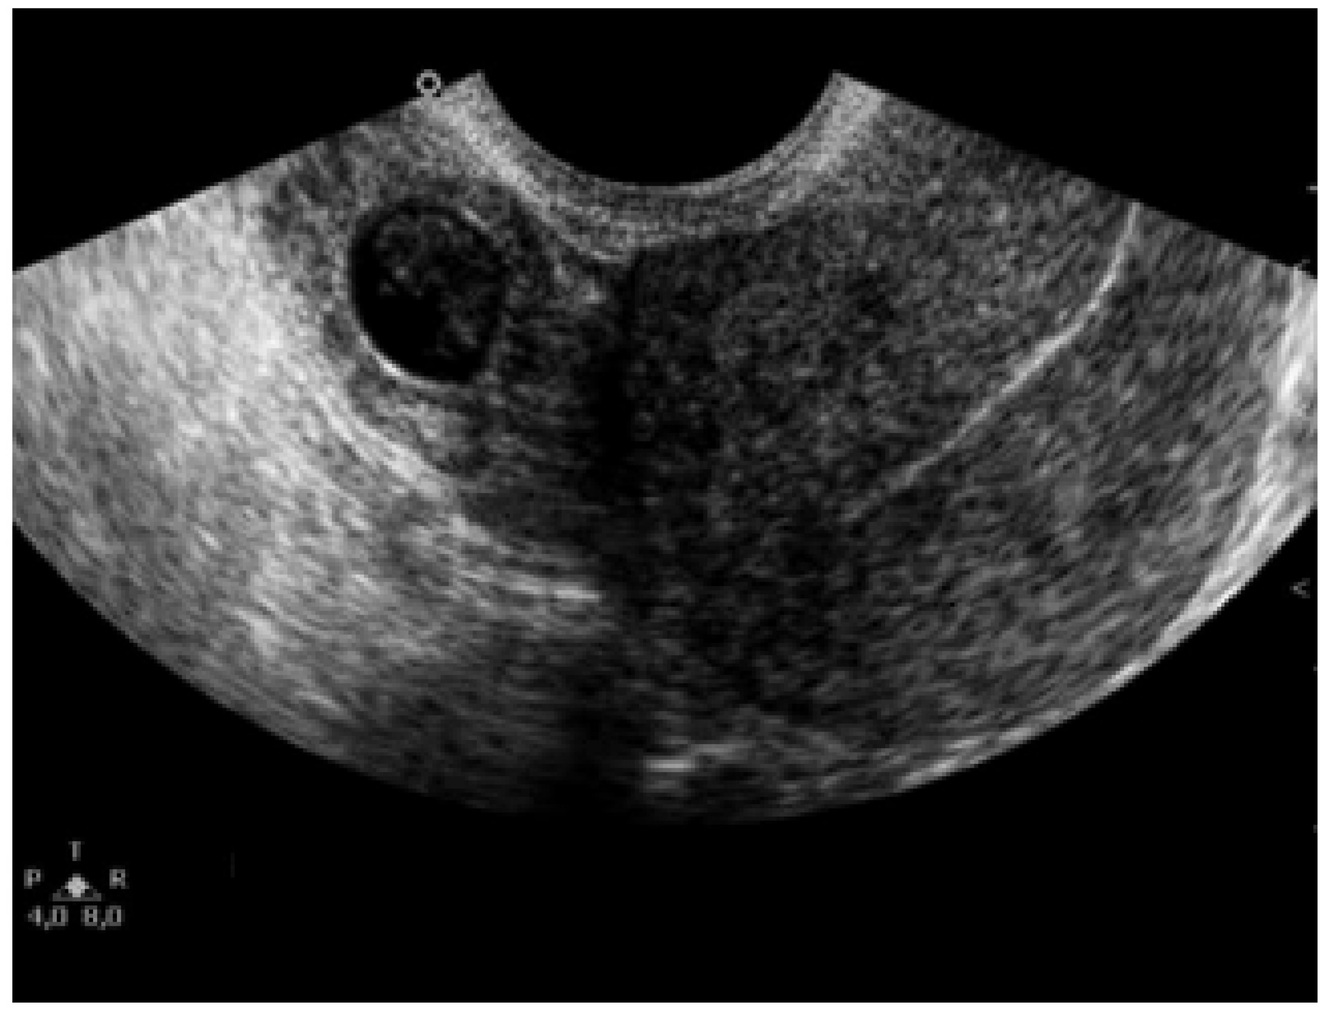

Dor em FID, sangramento, beta-HCG positivo e USG abaixo. Qual o diagnóstico?

A

Gravidez ectópica